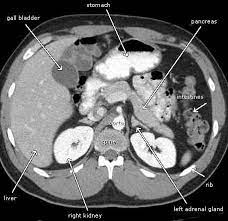

The abdominal CT scan is a powerful diagnostic tool that provides detailed images of the abdominal organs, revealing any abnormalities that might be causing discomfort. For Anita, this procedure was a crucial step in unveiling the hidden truths within her body. It promised to be the key to unlocking the mystery that had held her captive in a state of fear and uncertainty.

A few days later, Anita received a call from her doctor. Her heart raced as she listened to the verdict. The scan had revealed a small but significant issue a gallstone lodged in her bile duct. While the news was serious, it was a relief to finally have a name for her pain and a path forward.

Incorporating a case study from the bustling corridors of AIIMS, Delhi, we see a similar scenario where another patient, Ramesh, faced unexplained weight loss and fatigue. His abdominal CT scan revealed early-stage liver disease, allowing him to seek timely intervention and management. These real-life examples highlight the significance of abdominal CT scans in diagnosing conditions that might otherwise remain hidden until it's too late.